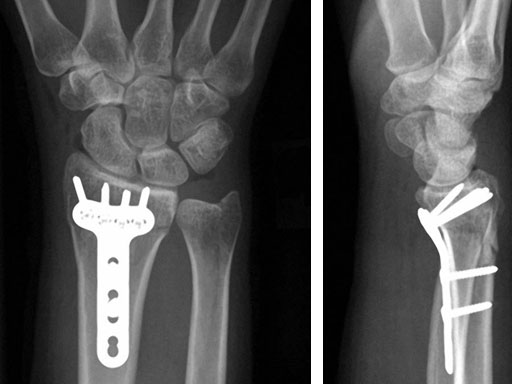

Fig 3ab X-rays 5 months postoperatively.